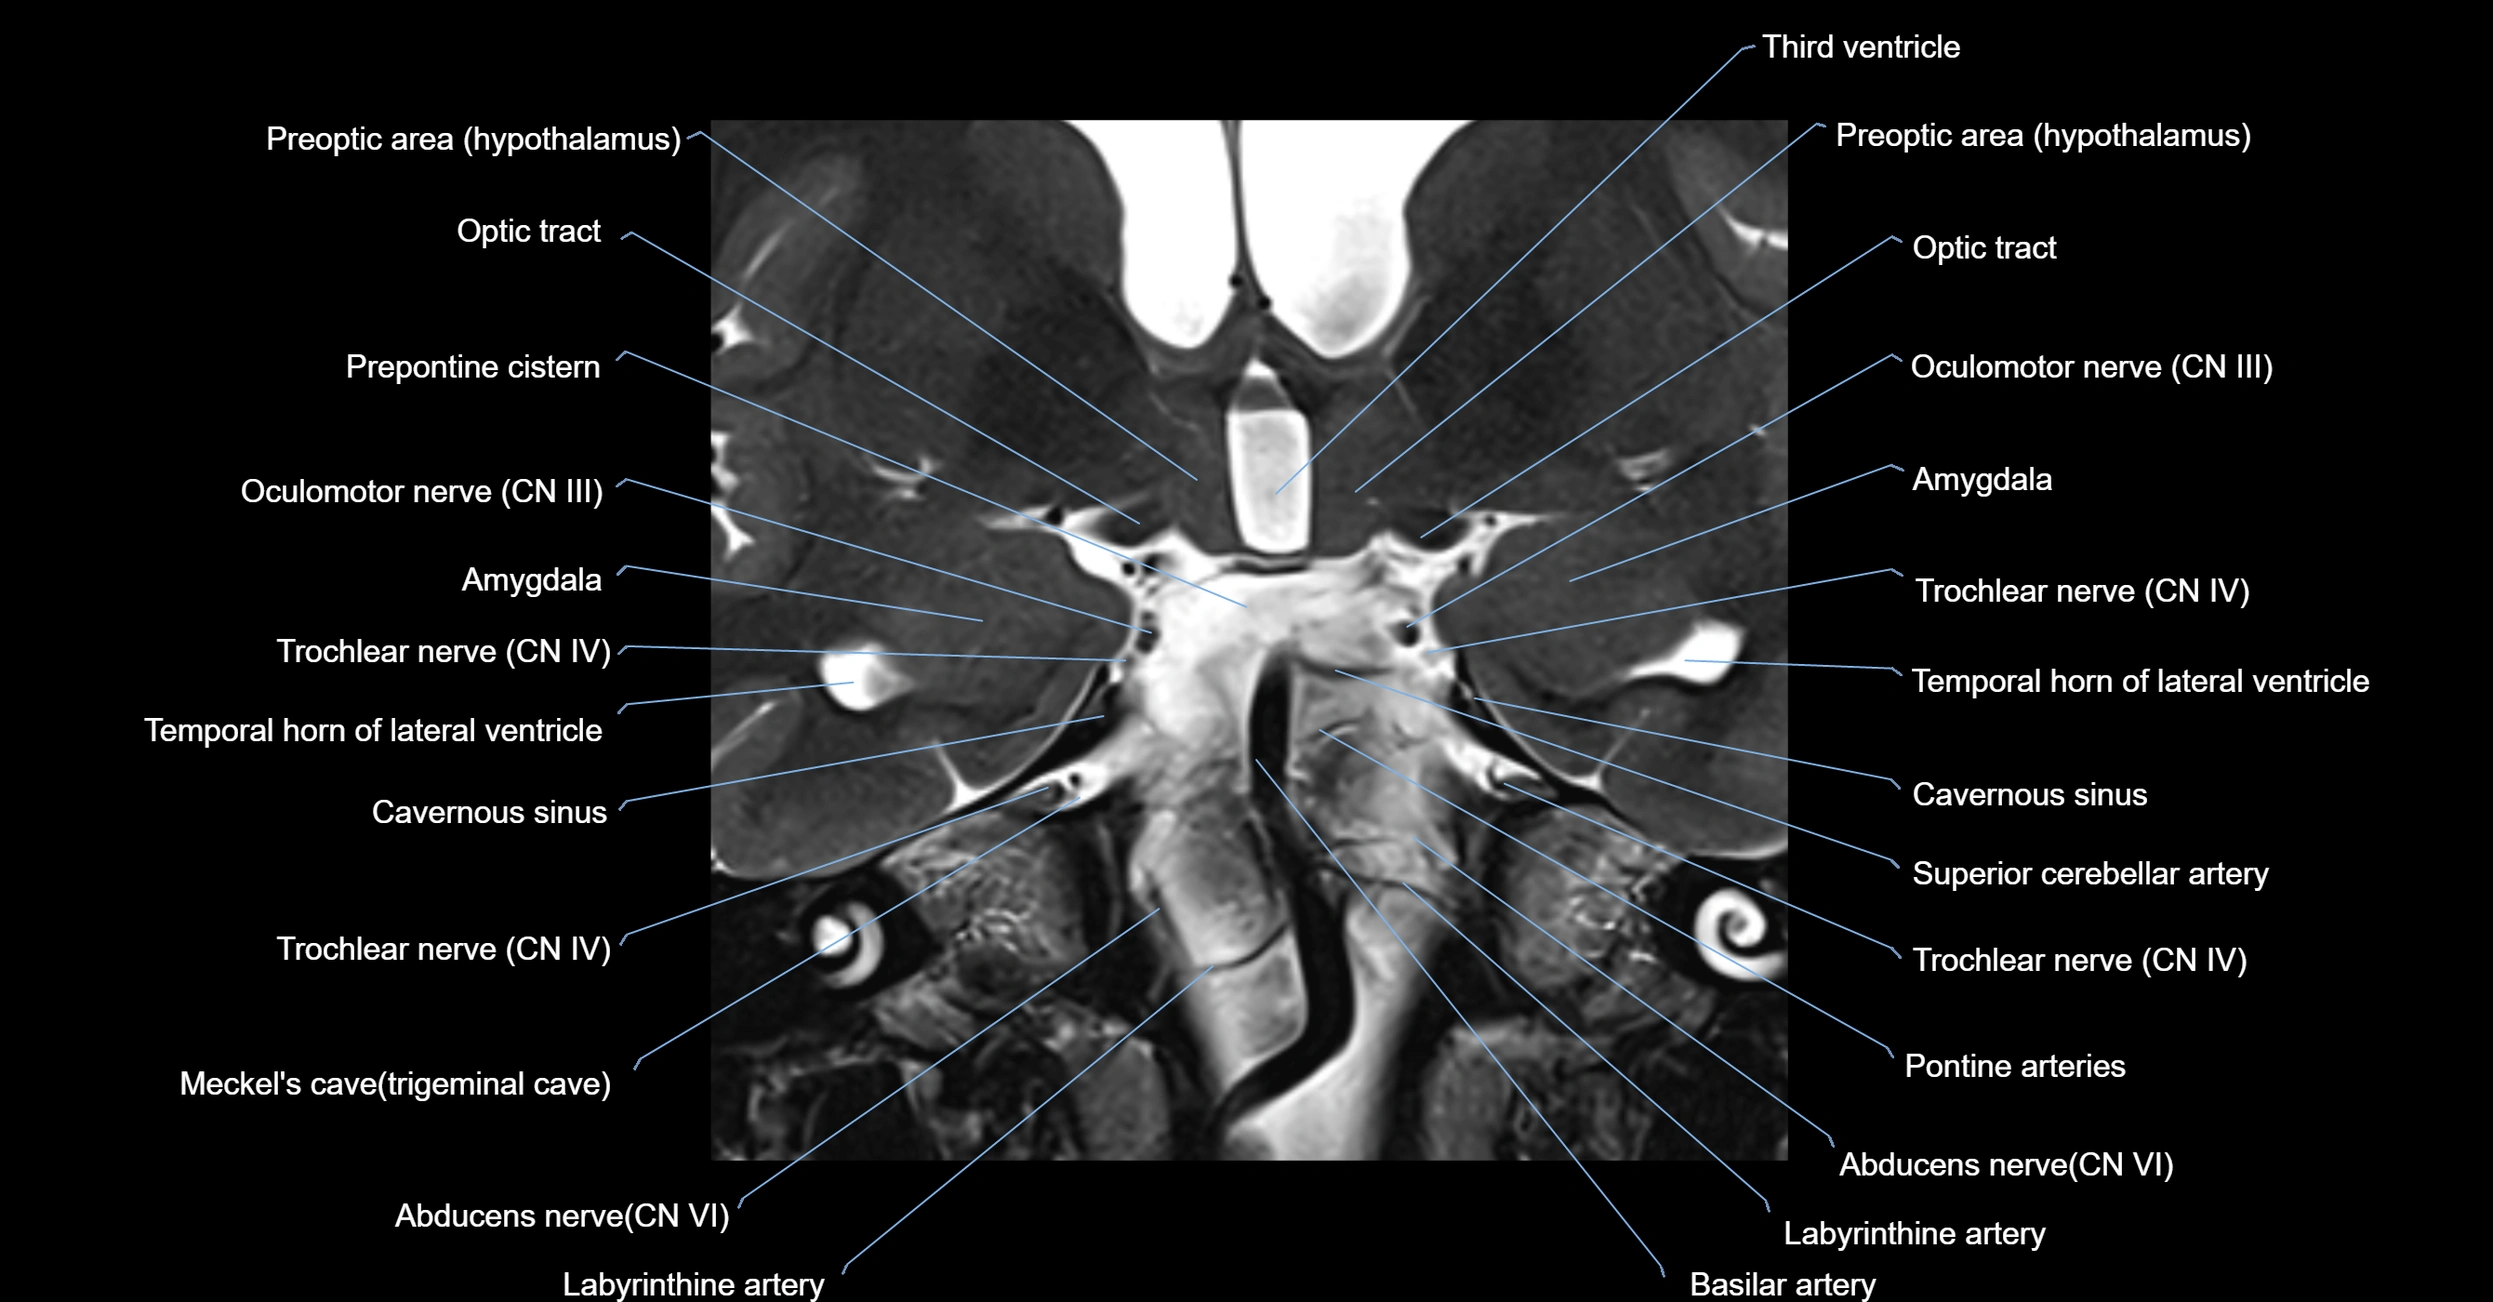

MRI Appearance

-

The abducens nerve is a small, thin, linear structure

Best visualized on high-resolution T2-weighted 3D MRI sequences (e.g., FIESTA or CISS)

Seen as a hypointense (dark) line running from the brainstem at the pontomedullary junction, traversing the prepontine cistern, and entering Dorello’s canal under the petrosphenoidal ligament, then into the cavernous sinus, and finally the orbit

May be challenging to visualize in standard MRI due to its small size

Pathology may be inferred by absence, displacement, or enhancement of the nerve

MRI images